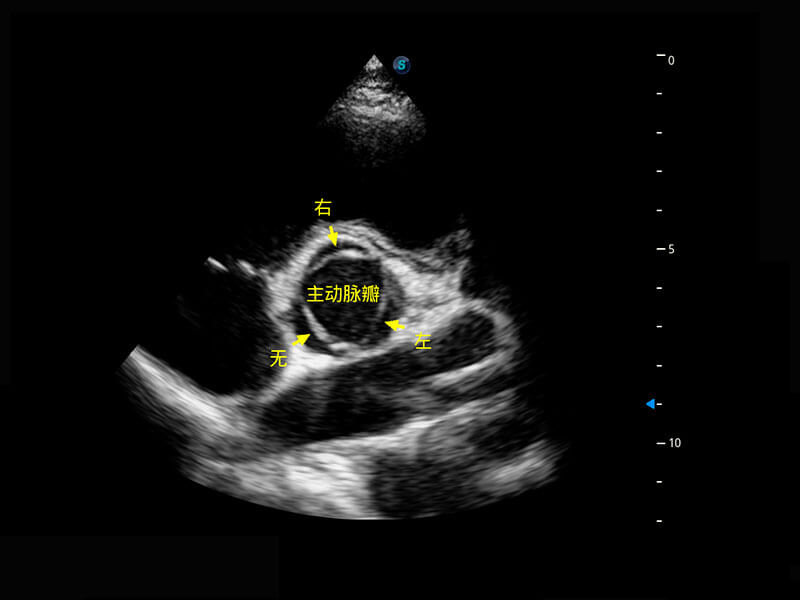

四腔切面

四腔心血流

右室双出口

胎心容积成像